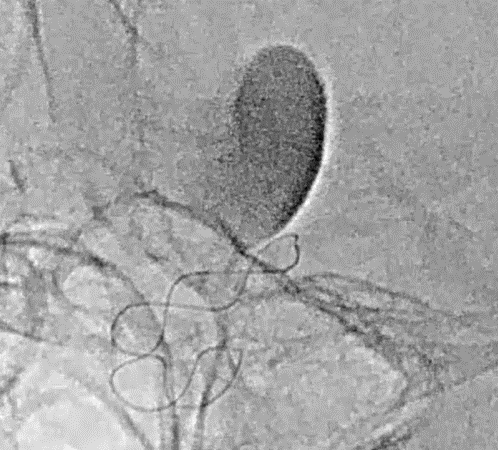

Tubridge Case 4